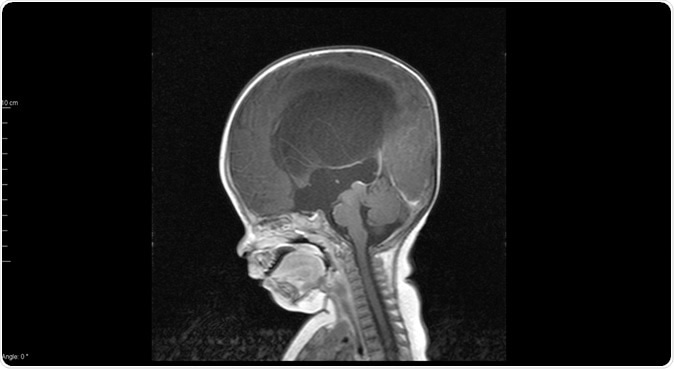

Sagittal MRI T1 showed mark hydrocephalus with congenital aqueductal stenosis - Image Credit: O_Akira / Shutterstock

Hydrocephalus affects about one in 500 babies at birth, and is the most frequent indication for brain surgery in childhood. It refers to a buildup of cerebrospinal fluid (CSF), the fluid which bathes the brain and spinal cord, around the brain. This compresses the organ and can cause permanent damage if not relieved. It can also happen in children or adults following a tumor which blocks the outlet of the CSF from the brain, or after meningitis.